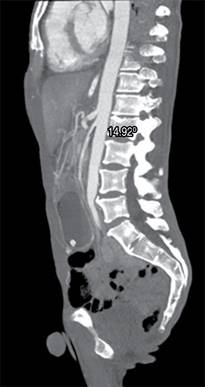

Se realizó tomografía de abdomen en la que se identifica dilatación gástrica con pérdida de los pliegues gástricos así como disminución de la distancia entre la arteria aorta y arteria mesentérica superior, la cual mide 8.05 mm (Figura 1). En el corte sagital de la tomografía se observa un ángulo agudo aortomesentérico de 14.92o (Figura 2). Desde su ingreso recibió manejo con descompresión gástrica con sonda nasogástrica, reposición hidroelectrolítica, analgésicos y antibioticoterapia con cefalosporinas de tercera generación; sin embargo, persiste la obstrucción a pesar de manejo conservador durante 48 horas, por lo que se propone y acepta manejo quirúrgico. Se realiza abordaje laparoscópico con cinco puertos, se moviliza el colon transverso y se visualiza el sitio de obstrucción secundaria a pinzamiento de la arteria mesentérica superior entre la tercera y la cuarta porción del duodeno. Se realiza duodenoyeyuno-anastomosis mecánica a 60 cm del ligamento de Treitz, se cierra gastroenterotomía en dos planos con monofilamento de absorción lenta para el primer plano y no absorbible para el segundo. Con buena evolución postoperatoria, inicio de líquidos a las 24 horas y progresión a dieta blanda a las 48 horas. Fue egresado por mejoría 48 horas después del procedimiento. En seguimiento postquirúrgico durante dos meses con adecuada tolerancia a la vía oral, no se cuenta con secuencia clínica posterior, ya que el paciente no asiste a control.

Figura 1: Tomografía contrastada. A) Corte axial donde se observa una distancia entre arteria aorta y arteria mesentérica de 8.05 mm. B) Corte coronal donde se observa dilatación gástrica con pérdida de los pliegues gástricos y amputación de la tercera porción del duodeno.